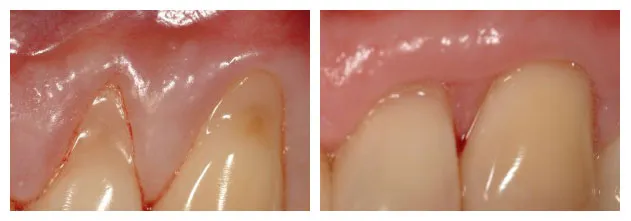

Gum recession and exposed roots.

Gum recession corrected

Covering Exposed Roots

Gum Graft to cover an exposed and sensitive tooth root